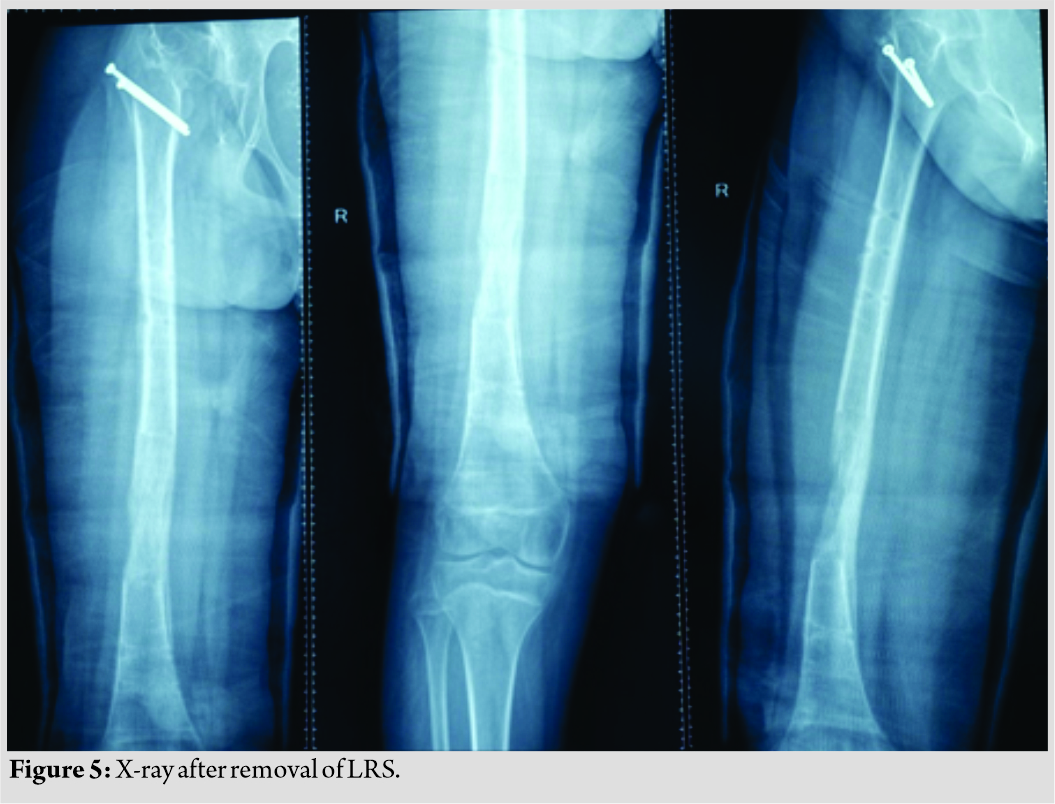

Care was taken to preserve the piriformis attachment on to main femoral fragment. With the help of patella holding clamp, the GT fragment was held and shifted to 2 cm distally and fixed with two 4 mm cannulated cancellous screws. The wound was closed over the suction drain and the patient was then planned for monorail external fixator in the supine position. Gradual distraction was started from the 5th post-operative day (Fig. 3).  Careful follow-up evaluation was done and distraction was stopped once limb length equalization was achieved (Fig. 4-6). The fixator was removed after 112 days. The patient had no complication postoperatively except mild pain during early phases of distraction which was managed with high-dose analgesics and knee stiffness in the later part of the distraction. She achieved a complete range of motion of knee with extensive physiotherapy and quadriceps strengthening exercises. At final follow-up of 6 months, the patient had no equinus at the ankle with improvement in hip abduction with minimal abductor lurch.

Careful follow-up evaluation was done and distraction was stopped once limb length equalization was achieved (Fig. 4-6). The fixator was removed after 112 days. The patient had no complication postoperatively except mild pain during early phases of distraction which was managed with high-dose analgesics and knee stiffness in the later part of the distraction. She achieved a complete range of motion of knee with extensive physiotherapy and quadriceps strengthening exercises. At final follow-up of 6 months, the patient had no equinus at the ankle with improvement in hip abduction with minimal abductor lurch.

The second patient, a 14-year-old male, presented to us with complaints of limping in the left lower limb without any pain in the hip joint. He also had a history of septic arthritis in the left hip which was managed non-operatively in a village hospital. There was no history of trauma, weight loss, or tuberculosis. On examination, it was found that the patient had limited terminal hip ROM with severe restriction in hip abduction (25°). There was a true shortening of 6 cm in the left femur and the patient walked with abductor lurch without any ankle equinus with excessive flexion in the opposite knee. An X-ray revealed severe coxa vara on the left side with increased acetabular index (Fig. 7). There was minimal joint space narrowing medially. The femoral diaphysis was thin as compared to the opposite side. The power of the muscles around the hip and knee was comparable to the opposite side. Based on these findings, it was classified as a case of Choi’s Type 2 septic sequelae of the hip with 6 cm of femoral shortening. The patient underwent trochanteric advancement distally as described in the previous case along with a simultaneous application of monorail external fixator and corticotomy in the distal femur. The distraction started on the 5th post-operative day in equal increments of 0.25 mm every 6 hourly (Fig. 8 and 9). After achievement of limb length equalization, the fixator was removed after 114 days. Three weeks after this, the patient presented with a fracture of the regenerate with minimal angulation and was managed further by one and a half spica cast for further 4 weeks (Fig. 10). At latest 12 months follow-up, the patient was walking normally with minimal abductor lurch.